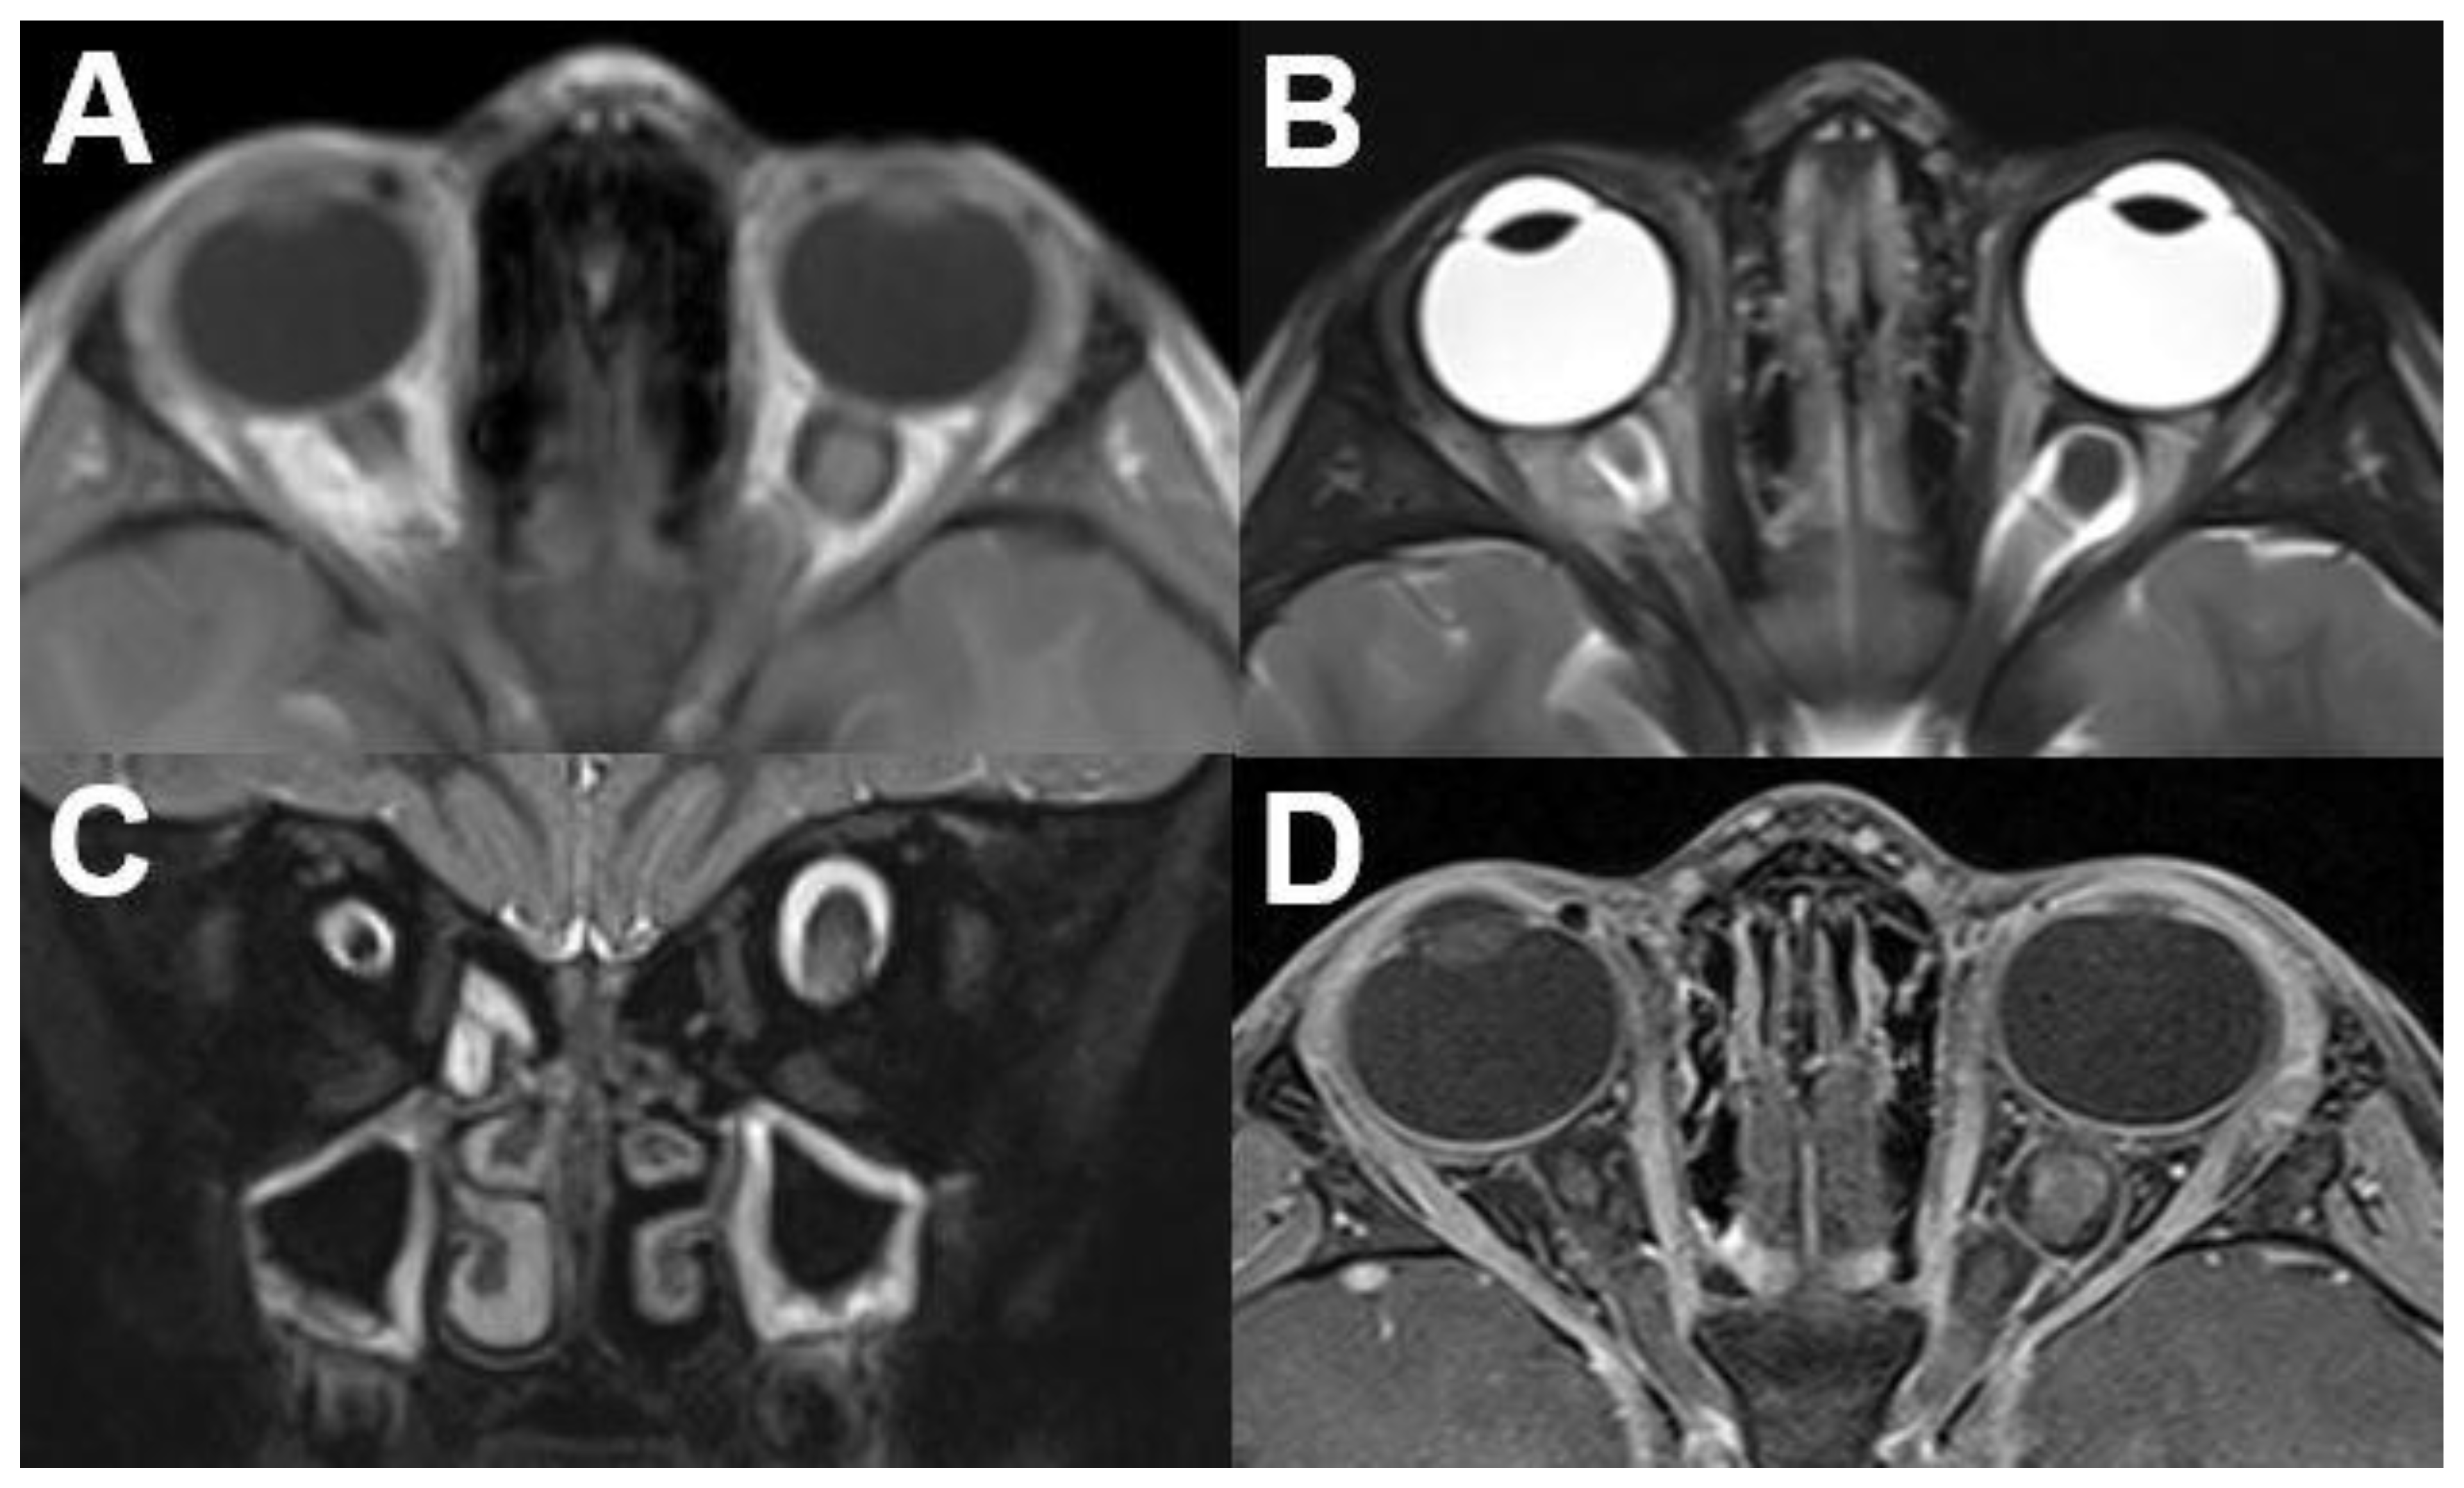

3.1.1. Retinoblastoma

3.1.2. Uveal Melanoma